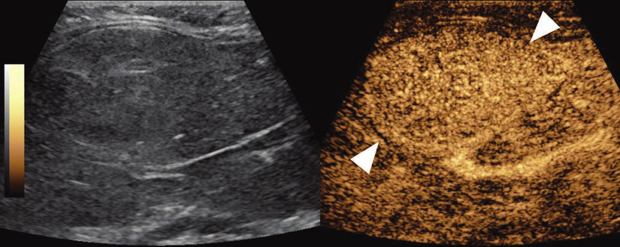

Consider your patients, as well: While a health care system might deploy sophisticated software to support their telehealth endeavors, this does not mean that all patients have the necessary hardware or software to participate. Additionally, solutions to barriers such as vision, language, and hearing must be readily available. One additional effort I applaud is to make our digital reports more comprehensible; not every patient understands what is meant by the phrase “the hepatic parenchyma demonstrates a normal echotexture,” nor should they. We should support software solutions to simplify the communication and accuracy of our recommendations.